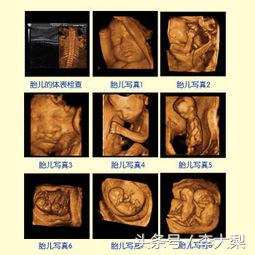

大梨推荐各位准妈妈们做四维彩超,简单地说,普通B超就像黑白照片,彩超就像彩色照片,而四维彩超就像是摄像机所拍摄的VCR。普通B超和彩超看到的只是一个平面,而四维彩超看到的是胎儿的动态立体图像,胎儿的前后、左右、上下都可以看到,更加全面、真实且清晰。能够有效的检测出宝宝脐带绕颈的情况,尽早的进行治疗。

宁波艾博尔医院引进美国GE四维彩超,这是目前世界上最先进的彩色超声设备之一,它能提供连续动态的视频和系统性的扫描,为准妈妈的健康保驾护航。

四维彩超图像